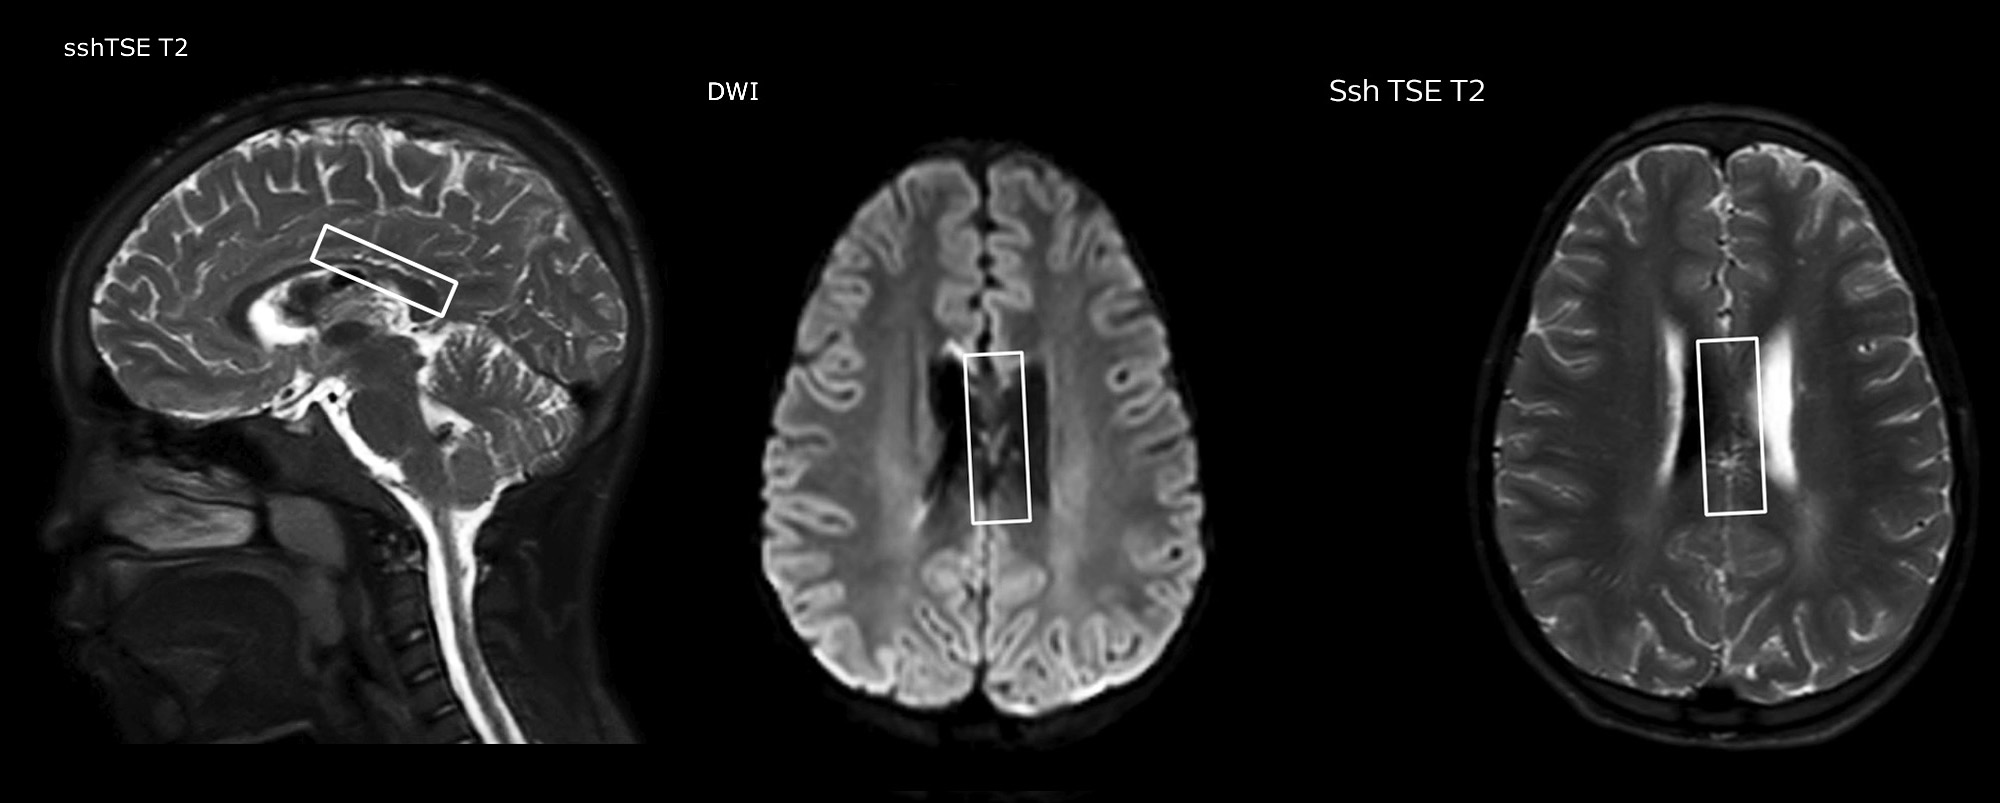

“In combination with diffusion weighted imaging, it can help give a more extended assessment of the degree of perfusion abnormality in a patient who is suffering acute ischemia. We have a number of patients who have chronic arterial insufficiency due to prior arterial abnormalities or acquired arterial abnormalities such as sickle cell disease or neurofibromatosis. Sometimes the child’s first manifestation of disease progression is a reduction in brain perfusion before stroke symptoms manifest clinically or in diffusion weighted imaging. We use pCASL to help delineate the perfusion abnormality.”

To other new users I would recommend to also start to interpret the pCASL images in comparison with other standard imaging – T2 and FLAIR and DWI – until the user gains confidence in interpreting these images by themselves.” “A powerful use of pCASL is in patients with chronic cerebrovascular stenosis, where clinicians desire information on how compensatory mechanisms of the brain are performing to enable perfusion to the brain. Often clinicians take into account how the compensatory mechanisms appear to help to provide adequate perfusion to the patient’s brain, and they may intervene surgically or make some other management decision.” “Another special application is the assessment of cerebrovascular reactivity with a Diamox perfusion exam, where we subtract two sets of pCASL images.”

“pCASL has now become more of a first-line scan for assessing perfusion for us, as opposed to DSC-based perfusion imaging with contrast agent. And in patients who were not planned to have contrast, we can perform pCASL for perfusion imaging without need to stop the exam, pull the patient out, and put in an IV. It also negates the postprocessing that’s necessary for dynamic susceptibility contrasts. And it allows us to repeat perfusion imaging in the same patient at the same imaging time, which is helpful in terms of patient motion, or in a situation where a scan needs to be done before pharmacological perfusion imaging.”